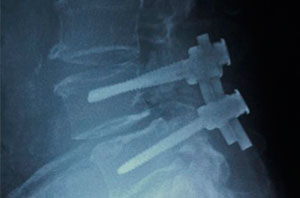

Me diagnosticaron escoliosis cuando tenía 13 años, en el año 2010 y ese mismo año me operaron en el mes de octubre. Al inicio, no me gustó la idea de la operación porque interfería con algunos planes que ya tenía en mente, pero sabía que si quería estar bien, tenía que sacrificarlos porque más importante era mi salud.  No muchos doctores saben de esta enfermedad, gracias a Dios conocí al Dr. Cárdenas que fue muy amable y amigable conmigo y me explicó con todo detalle como sería la intervención; así que más que miedo, sentía emoción porque llegara el día.

Después de mi operación, solo estuve internada 4 días. Tengo 11 tornillos en mi columna y ya llevo 5 años de operada; vivo una vida normal y soy feliz.